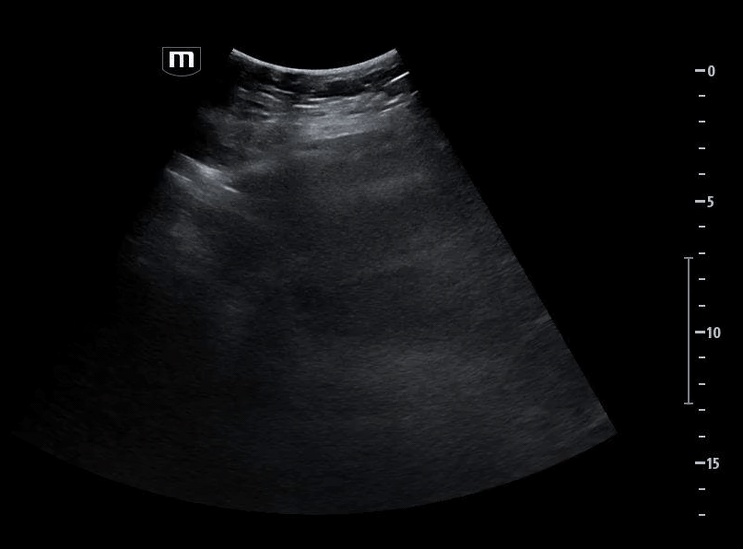

She isn’t crashing—but she isn’t stable either. Luckily, an ultrasound is immediately available. An eFAST exam is performed, revealing the following:

Image 2 confirms this finding using M-mode, demonstrating the classic barcode sign, which is consistent with absent pleural motion.